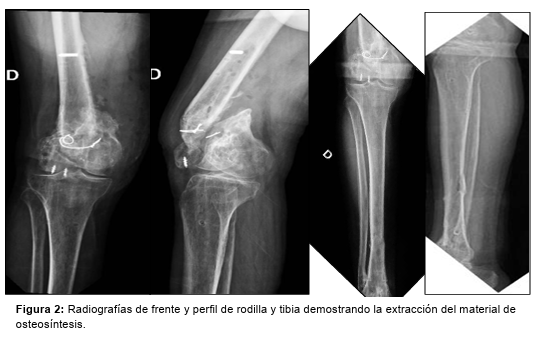

En una primera instancia se extrae el material de osteosíntesis, tomándose muestras para directo, cultivo y antibiograma, y se realiza toilette quirúrgica (Figura 2).